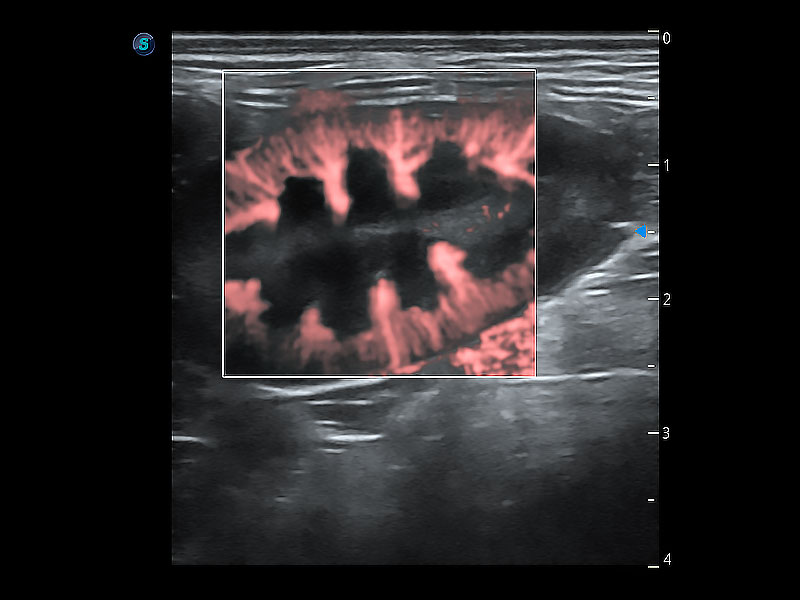

• Bright Flow 立体血流成像

在传统二维血流成像的基础上,呈现血流的立体感,具有动感的生命力之美。即便是微小的血管也能轻松应对,提高了血流的视觉敏感性。

(犬)肾脏显微血流

优异的基础图像

ProPet 80 全新的动物超声智能软件和丰富的探头群,为动物医生提供了高清晰度和精细分辨率的图像,无论在宠物、马科、畜牧还是实验室动物等应用中都可以轻松应对,为您的日常工作带来满意的体验。